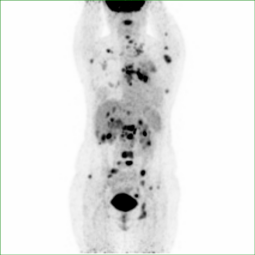

全身PET/CT显像异常图像(肺癌伴全身多处转移):